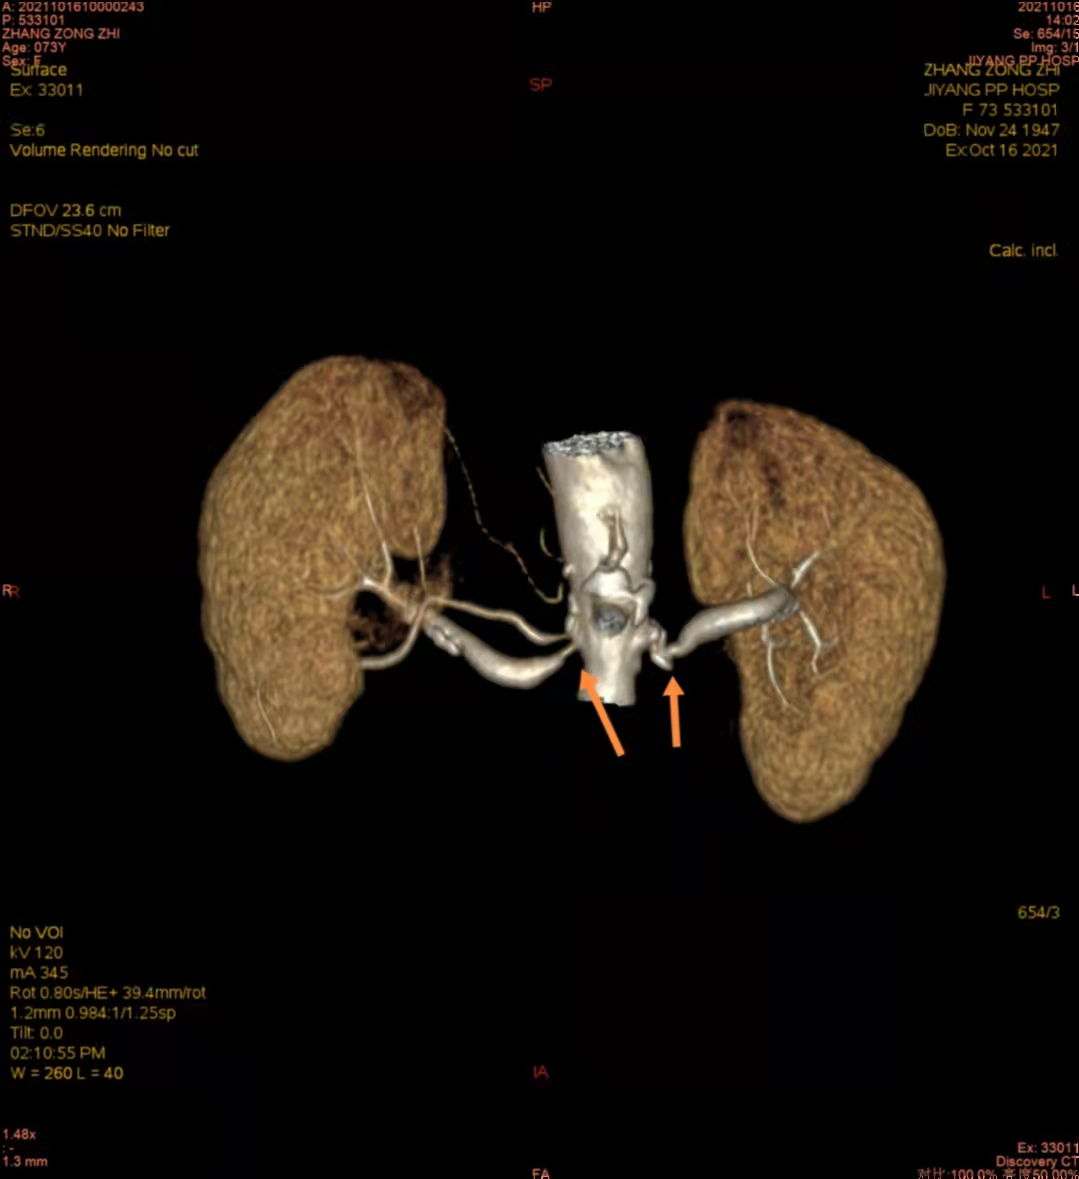

注:CTA下右侧肾动脉重度狭窄;左侧肾动脉起始段混合

斑块形成、管腔重度狭窄